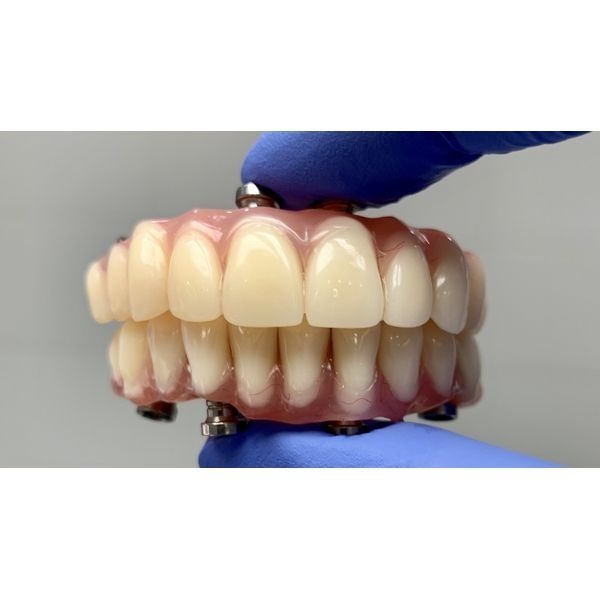

Через неделю пациентка пришла на плановый осмотр, во время которого ей сняли швы. В течение трёх месяцев она питалась жидкой и мягкой пищей, чтобы снизить нагрузку на импланты.

Полгода женщина носила временную конструкцию. За это время она дважды делала контрольные ортопантомографические снимки и компьютерную томографию, чтобы контролировать состояние полости рта. Когда импланты прижились, ей поставили постоянный протез.

Результат лечения полностью удовлетворил пациентку: она избавилась от проблем с дикцией, перестала ограничивать себя в еде и стала более уверенной. Теперь каждые полгода женщина приходит на профилактический осмотр и гигиену полости рта.

Постоянный протез нельзя устанавливать сразу после имплантации, так как имплантам требуется время (от 2 до 6 месяцев) для успешного приживления и заживления десны. Чтобы не оставить пациента «без зубов», ему предлагают использовать временную конструкцию.

Этот случай наглядно показывает пользу такого метода, ведь во время адаптации пациентка могла не переживать насчёт своего внешнего вида и работы челюстей.